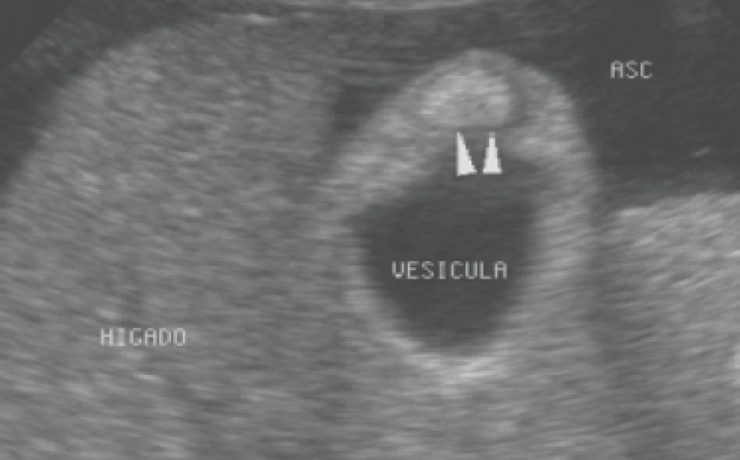

DIAGNOSTICO ECOGRÁFICO PRENATAL DE HEPATOBLASTOMA.

Las lesiones focales en el hígado en niños de 0 a 3 años incluyen neoplasias, lesiones metastásicas, masas inflamatorias y quistes (congénitos o adquiridos); las neoplasias primarias tanto benignas como malignas representan 1 a 2% de todos los tumores pediátricos. El hepatoblastoma es el tumor hepático maligno más frecuente en